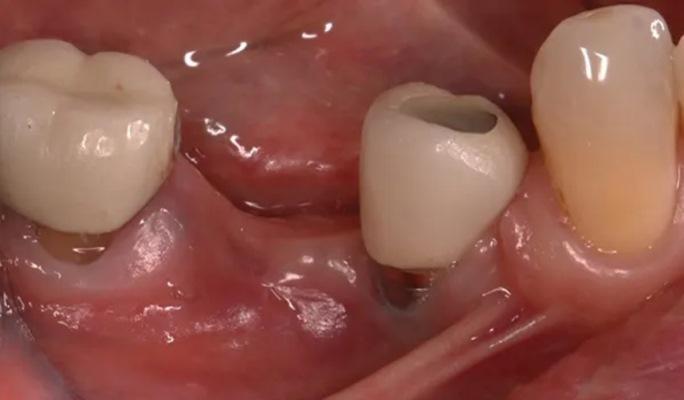

Во время консультации в 2016 году при внутриротовом осмотре выявлено большой обьем потери как вертикальной, так и горизонтальной резорбции (класс III по Зайберту) 12 мм в области отсутствующего имплантата 4.5 (фото 3 – фото 5), в области имплантата зуба 4.4. диагностировано обнажение четырех витков имплантата с дистальной стороны и двух витков с щечной стороны.

Фото 3. Показано место отсутствующего имплантата 4.5. со стороны щеки.